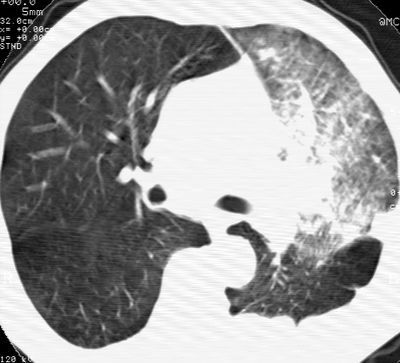

左肺门肿块,相应支气管闭塞,左肺上叶、舌叶大片及散在高密度影,部分呈不张改变,两肺纹粗乱,左侧胸腔积液。考虑左侧中央型肺癌伴阻塞性改变。

左肺门见巨大软组织肿块影,直径约--,境界清,左上肺叶支气管变窄,左上肺舌叶见大片状密实影,余肺纹理增多、紊乱、纤细、部分网格状,两肺透亮度增高,纵隔内见增大多发淋巴结影,心影略左偏,左侧少量胸腔积液。

左侧中央型肺癌伴左上肺舌叶不张、纵隔淋巴结转移,左侧少量胸腔积液。